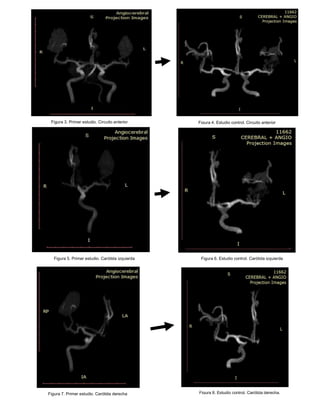

Figura 6. Estudio control. Carótida izquierda

Figura 3. Primer estudio. Circuito anterior Figura 4. Estudio control. Circuito anterior

Figura 5. Primer estudio. Carótida izquierda

Figura 7. Primer estudio. Carótida derecha Figura 8. Estudio control. Carótida derecha.

Figura 9. Primer estudio. Circuito posterior

Figura 9. Estudio control. Circuito posterior

Discusión: La demostración de “imágenes como en sacacorchos” o estrechez segmentaria

y multifocal en la angiografía cerebral representó el pilar diagnóstico y enfoque terapéutico